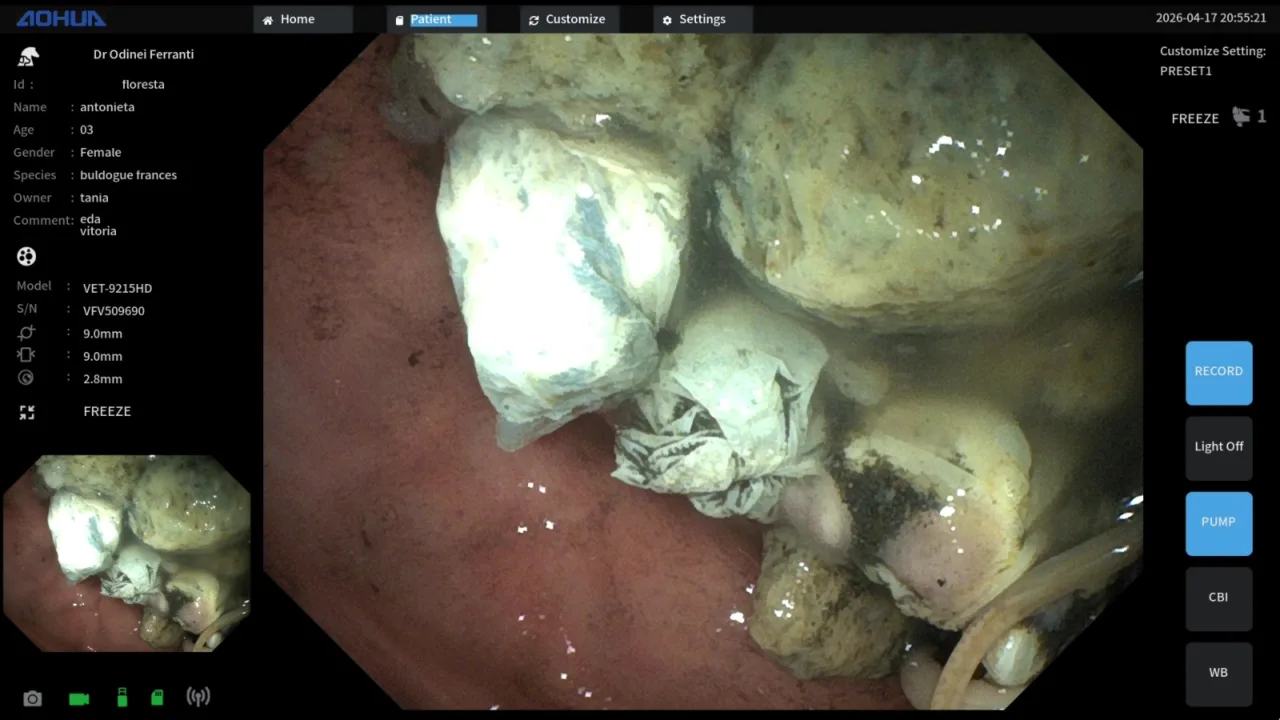

Mas, diante da suspeita de que ainda havia mais substâncias no organismo, foram realizados exames de imagem, como raio-x e ultrassom, que confirmaram a presença de mais pedras no estômago. Segundo a veterinária, a equipe optou por realizar uma endoscopia, procedimento no qual foram retiradas outras cinco pedras. Em seguida, foi feita uma lavagem gástrica e a aplicação de carvão ativado, técnica, que de acordo com a veterinária, é utilizada para reduzir a absorção de toxinas no organismo.